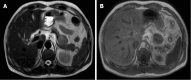

Case summary: We report on a rare case of CCS with pancreatic metastasis in a 47-year-old man. The patient had a relevant medical history 3 years ago, with abdominal pain as the main clinical manifestation. No abnormalities were observed on physical examination and the tumor was found on abdominal computed tomography. Based on the medical history and postoperative pathology, the patient was diagnosed with CCS with pancreatic metastasis. The patient was successfully treated with surgical interventions, including distal pancreatectomy and splenectomy.